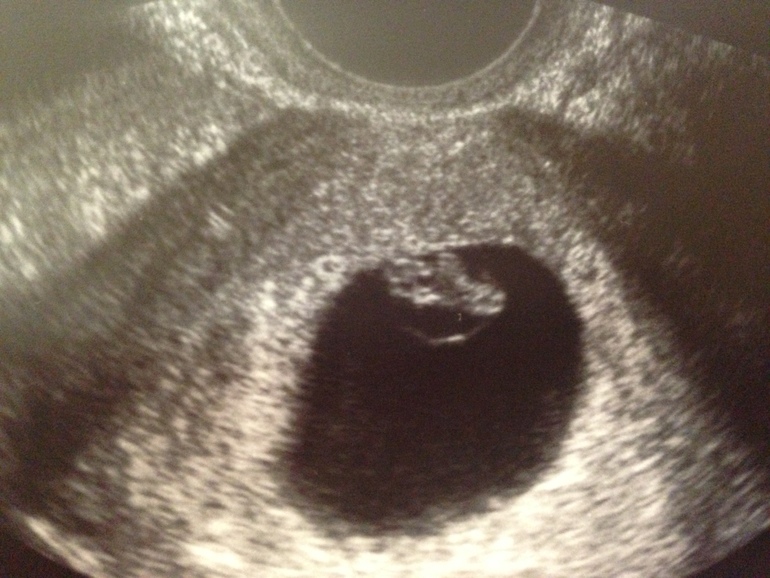

Только пришла с узи, всё хорошо.. и, кажется, страх пережитой ЗБ отступает...

Нам 7 недель и 3 дня и вот какие мы деловые :)